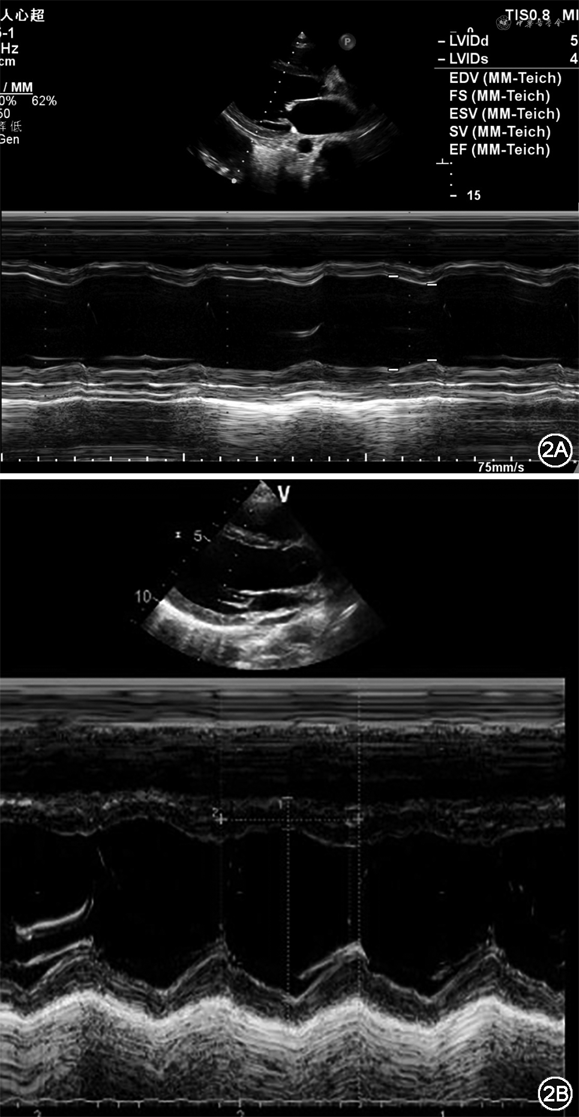

住院第2天(11月26日)超声心动图示:左心房前后径(left atrial diameter,LAD)39 mm,左心室舒张末期内径(left ventricular end-diastolic diameter,LVEDD)55 mm,左心室射血分数(left ventricular ejection fraction,LVEF)39%。超声心动图结论:符合心肌受累疾患超声改变,全心增大伴二三尖瓣少量返流,轻度肺动脉高压,少量心包积液(图2A)。床旁胸片提示:全心增大伴双侧胸腔积液(图3A)。26日上午室速再发,心室率130次/分,在静脉基础上加用口服维拉帕米80 mg,3次/d。夜间出现频发室性期前收缩(室早),R on T,随即演变为室颤(图1C和图4),患者抽搐,电除颤1次转为窦性心律,仍见频发R on T室早,后以利多卡因50 mg静脉注射,后以4 mg/min静脉泵入,室早明显减少;即刻查血钾3.84 mmol/L,血钠133 mmol/L,血镁0.99 mmol/L。当天查心电图提示:QTc=541 ms(心率78次/分)。

住院第5天(11月29日)心电监护提示有长13 s的尖端扭转性室速(Torsade de pointes,Tdp)发作,但自行转复,患者无意识丧失,仅有头晕不适。复查心电图:QTc=528 ms(心率80次/分)。当日复查血钾4.0 mmol/L,血钠135 mmol/L,血镁1.09 mmol/L。加用美西律200 mg,4次/d口服,停用利多卡因,加用酒石酸美托洛尔12.5 mg,2次/d,沙库巴曲缬沙坦25 mg,2次/d。床旁超声心动图提示:LVEDD 47 mm,LVEF 42%。

住院第10天(12月4日)安排患者出院,出院时心电图(图1D):QTc=483 ms(心率49次/分)。复查胸片(图3B)提示:双侧胸腔积液消失,心影明显回缩。复查床旁超声心动图示:LVEDD 47 mm,LVEF 49%。NT-proBNP 154.8pg/mL。